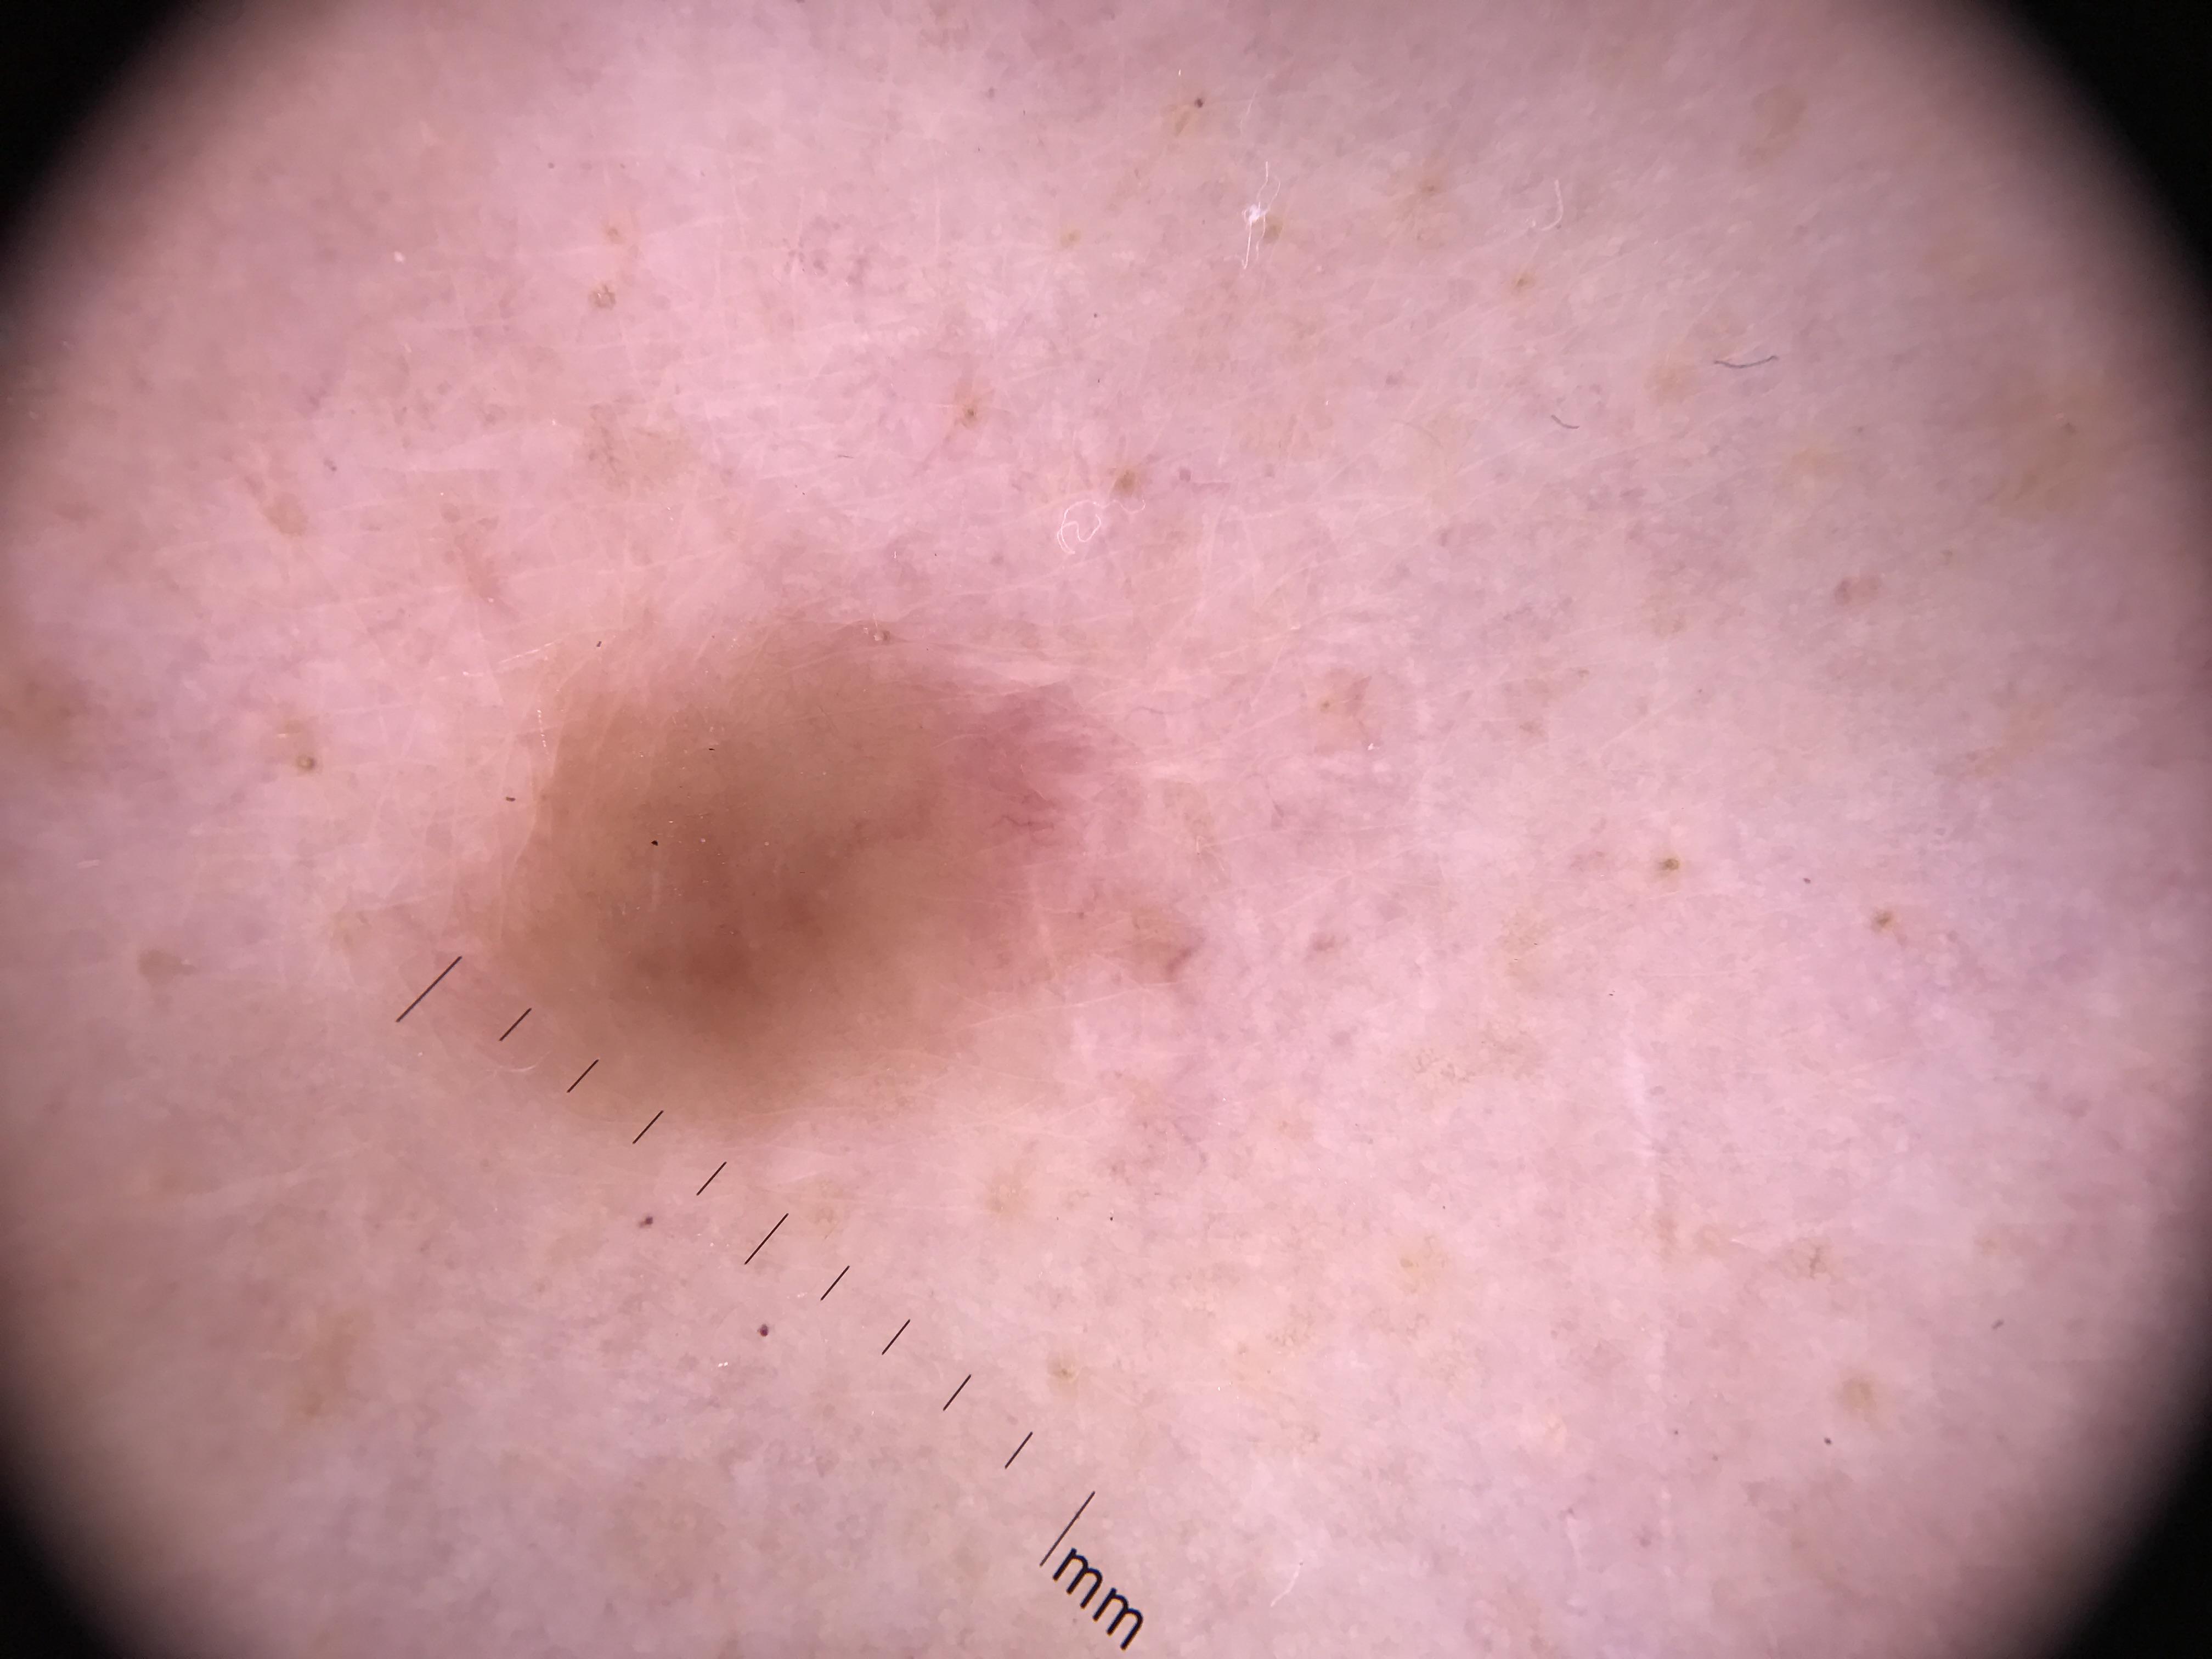

ISIC_7553924

Clinical

| Field | Value |

|---|---|

| diagnosis_1 | Benign |

| diagnosis_2 | Benign melanocytic proliferations |

| diagnosis_3 | Nevus |

| diagnosis_4 | Nevus, Atypical, Dysplastic, or Clark |

| diagnosis_5 | Nevus, Dysplastic |

| image_type | dermoscopic |

| melanocytic | True |

| patient_id | IP_4693375 |